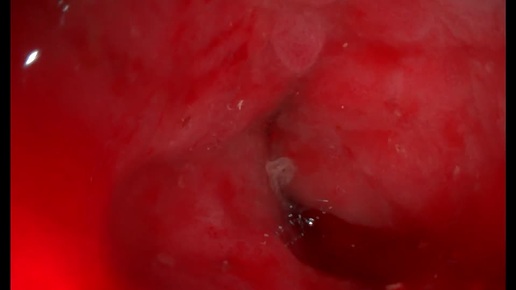

Декомпенсированный стеноз толстой кишки. (Врастание извне? Болезнь Крона? Tr?)